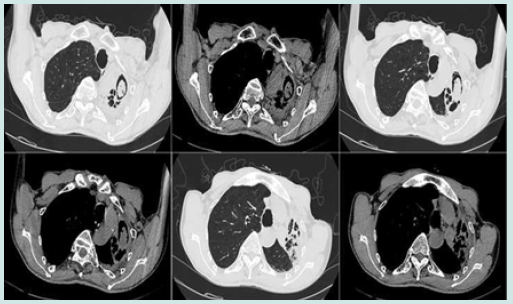

However, he developed fever after endobronchial instillation of amphotericin B, was given appropriate antipyretics, and granulation tissue proliferated 5 days after catheter placement (Figure 3D) without other significant systemic or additional complications. After 1 month of follow-up, a CT scan showed vacuolation of the left upper lobe lesion, forming an air moon sign (Figure 4), and the necrotic area had been resorbed. In addition, the patient’s haemoptysis had stopped and he recovered well. After discharge, the patient decided to stop taking oral voriconazole on his own after one month. To date, the patient is in good health with no clinical recurrence.

Figure 4: Follow-up CT image showed lesion of left upper lobe undergo cavitation and formation of the air crescent sign.